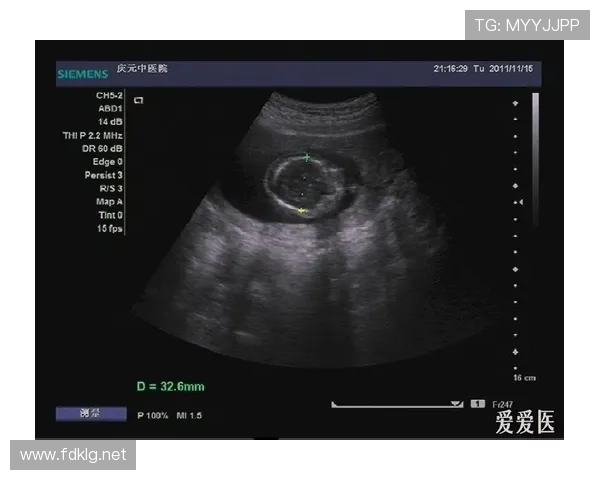

怀孕b超mt是一项诊断性检查,全称为妊娠期B超检查和测定胎儿MT值。主要用于评估母体妊娠情况、判断胎儿健康状况和测定胎龄。

B超检查是超声波检查的一种,是一种非手术的诊断性检查。通过B超检查,可检测到人体内脏各器官是否有病变。crl是指从胎儿头部到臀部的长度,又称为“头臀长”。怀孕7世界杯体育赛事-11周的这个期间,每个胎儿发育状况还没有太大差异,因此医院往往通过测量CRL来预测预产日。